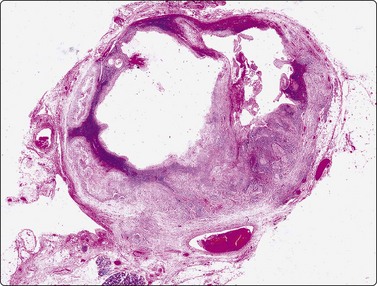

image image image image

Fig. 4.2 Cystically degenerate metastasis of well-differentiated squamous carcinoma

(A, B) Exfoliating atypical cells of ‘parakeratotic’ type in FNB smear and corresponding tissue section; (C, D) Other example with predominance of anucleate keratinized cells and clumps of keratin in the cyst lumen.

Fig. 4.3 Cystic metastasis of squamous carcinoma

Whole section of cervical lymph node containing metastatic deposit of squamous carcinoma with central cystic degeneration. Note similarity to branchial cyst (HE).

The diagnostic difficulties are due to the fact that squamous epithelial cells aspirated from a cystic metastasis of well-differentiated SCC are often anucleate or of parakeratotic type with a mature cytoplasm and a small pyknotic nucleus appearing cytologically bland, while inflammation of a benign cyst can result in immature squamous metaplasia and worrying cytological atypia. Figures 4.1 and 4.2 compare cells exfoliating from the lining of inflamed branchial cysts with those from cystic SCCs seen in histological sections. Helpful clues are that material sampled from a cystic SCC is more obviously necrotic than inflammatory, and a careful search usually reveals a few squamous epithelial cells with malignant nuclear features or abnormal keratinised cells with bizarre, globoid shapes and dense orangeophilic (Pap) cytoplasm. The nuclear atypia and hyperchromasia seen in squamous cells from a benign cyst is of degenerative type. But the distinction is not always easy (see Figs 4.1C and D). In some cases, the FNB can only be reported as indeterminate. The only ancillary test we have found useful in this setting is HPV DNA sequencing. Occult tonsillar carcinomas and other oral cavity carcinomas with cystic lymph node metastases are a common clinical problem. Many such carcinomas contain HPV DNA as evaluated by PCR or other molecular testing and a positive result in an FNA sample is strong evidence that a lesion is metastatic carcinoma rather than a branchial cleft cyst or other benign cyst.